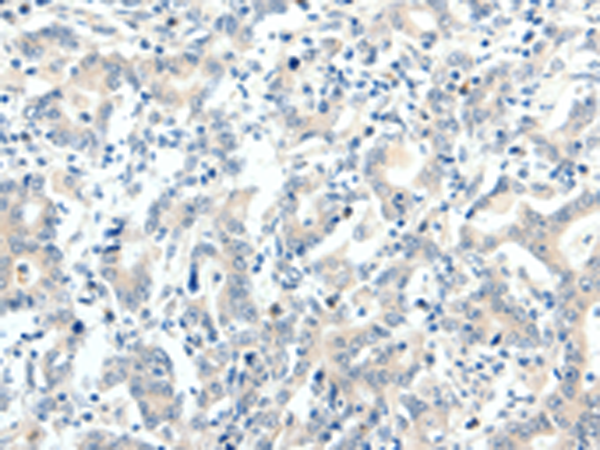

分类: 科研抗体货号: P04153别名: NTCP应用: IHC反应种属: Human, Mouse

分类: 科研抗体货号: P04198别名: R16; AAAT; ATBO; M7V1; RDRC; ASCT2; M7VS1应用: IHC反应种属: Human

分类: 科研抗体货号: P04195别名: NBC2, NBC3, SBC2, NBCN1, SLC4A6应用: IHC反应种属: Human, Mouse, Rat

分类: 科研抗体货号: P04223别名: TOP2; TP2A应用: IHC反应种属: Human, Mouse, Rat